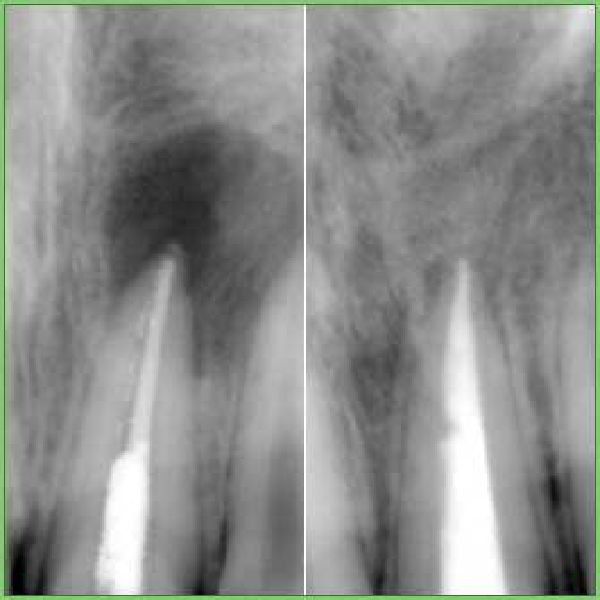

si può effettuare un'endodonzia immediata detergendo, sagomando ed otturando in un'unica seduta l'intero sistema di canali radicolari, anche nel caso di denti con ascesso in corso. La risoluzione delle lesioni apicali diventa veloce e risolutiva..